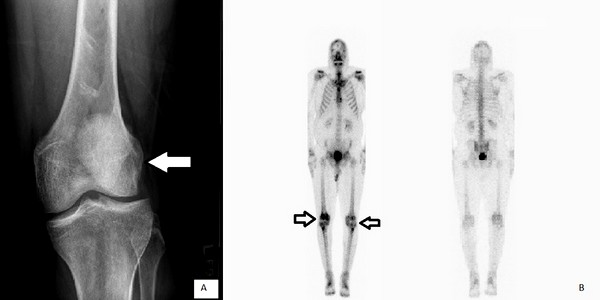

Рентгеновские снимки остеосклероза костной ткани